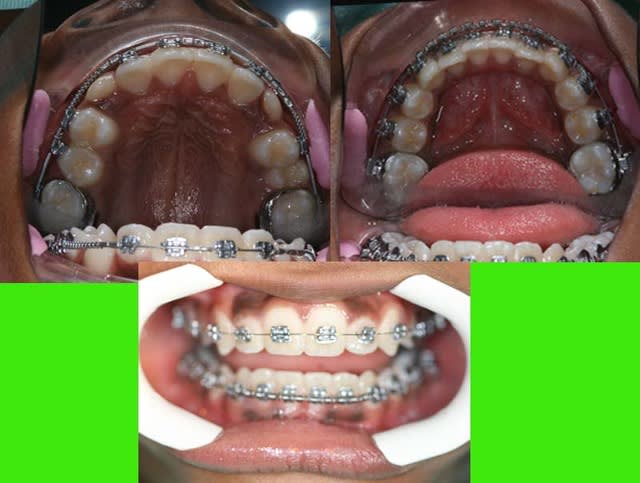

si ce n’était pas moi qui présentait ce cas (10 ans)

vous penseriez extractions ou pas d’extraction

P.S. : désolé, la photo en bas à droite est inversée

Photos du cas

voici les photos du m jour

bouche fermée

bouche ouverte

arcades